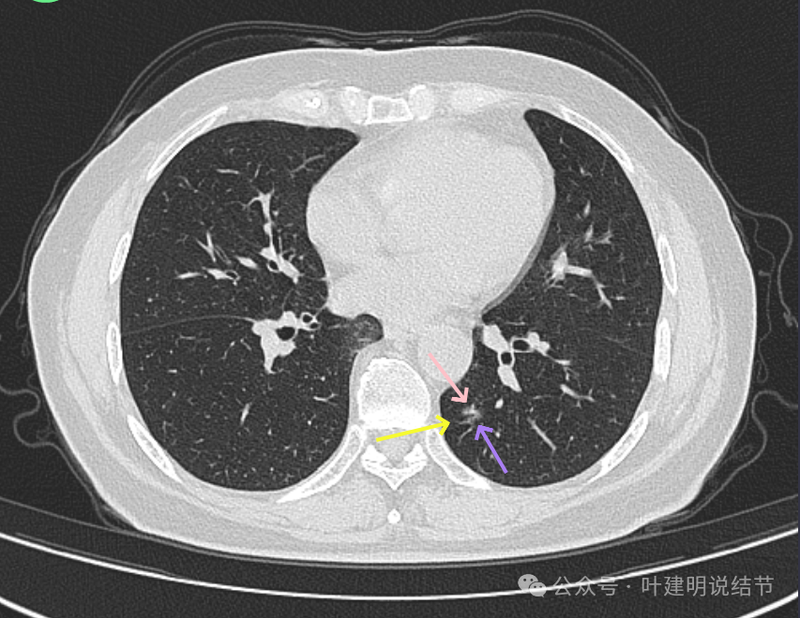

细支气管扩张以及边缘细毛刺,整体轮廓清。

磨玻璃密度伴少许偏实性成分,有微小血管进入。

边缘区密度淡,但轮廓仍清。